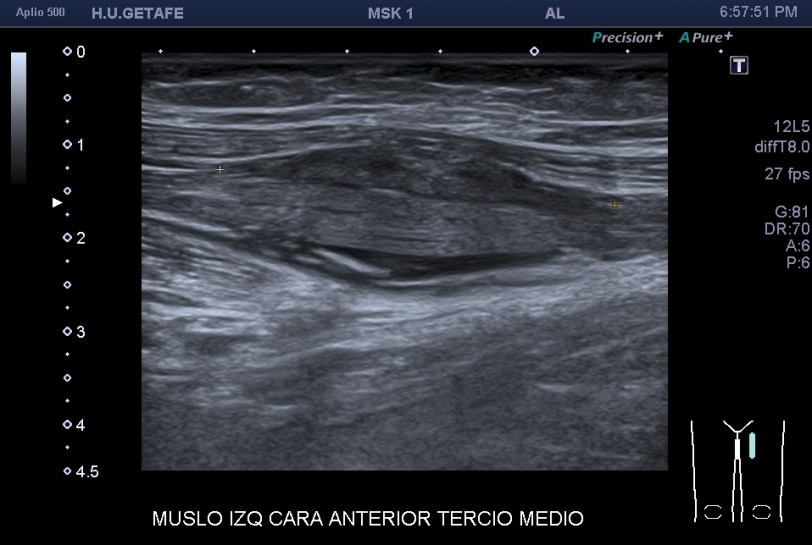

Después de estudiar la rotura en dos planos (imagen 1 y 2) y medirla (imagen 3 y 4), documentarla bien referenciándola con la anatomía locorregional, incluidos los vasos (imagen 5), decidí seguir el recorrido del músculo partiendo desde la rotura siguiendo las instrucciones que me había comentado la paciente y me dí cuenta que el músculo afectado cruzaba el muslo desde el tercio proximal del muslo, en la cara anterior de la cadera (en su porción más superficial) hasta la cara interna de la pierna…en concreto desde la espina iliaca antero superior y terminando en la inserción de la Pata de Ganso.

Medidas en eje corto.